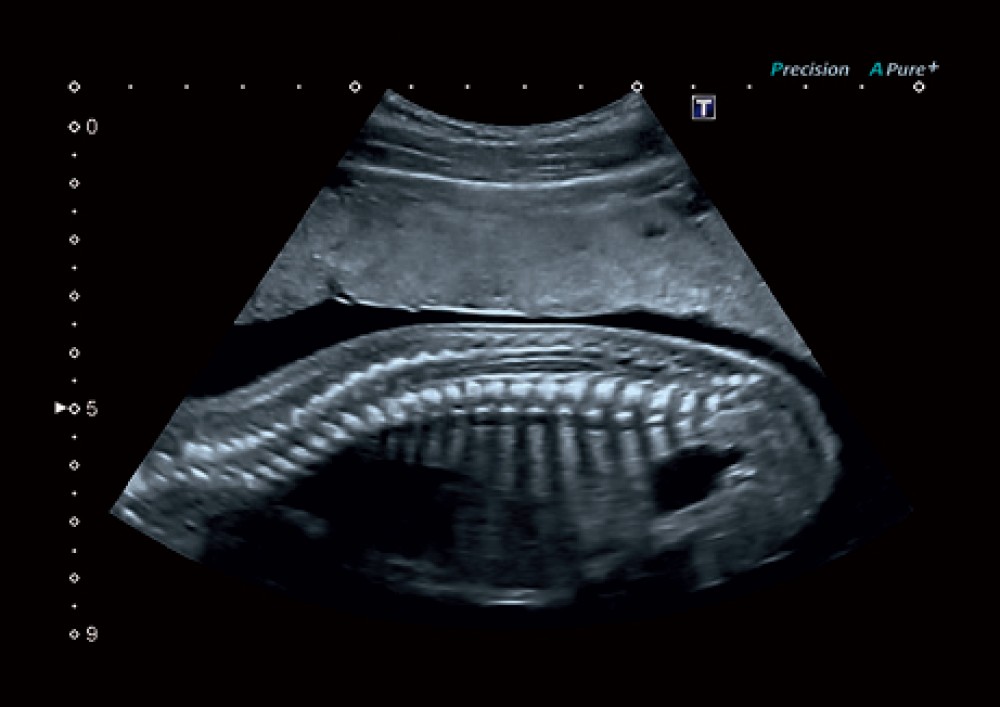

ApliPure™+: Məkan və tezlik kompozisiyasını birləşdirərək daha vahid və aydın görüntülər yaradır.

3D/4D görüntüləmə: Həcmi görüntüləmə ilə anatomik strukturların daha detallı qiymətləndirilməsinə imkan verir.

Toshiba Aplio 300 — mama-ginekologiya, kardiologiya, muskul-skelet sistemi və digər geniş klinik sahələr üçün nəzərdə tutulmuş yüksək səviyyəli ultrasəs sistemidir. Bu cihaz inkişaf etmiş görüntüləmə imkanları, erqonomik dizaynı və müxtəlif tibbi mühitlərə uyğunlaşdırıla bilən çevik platforması ilə seçilir.